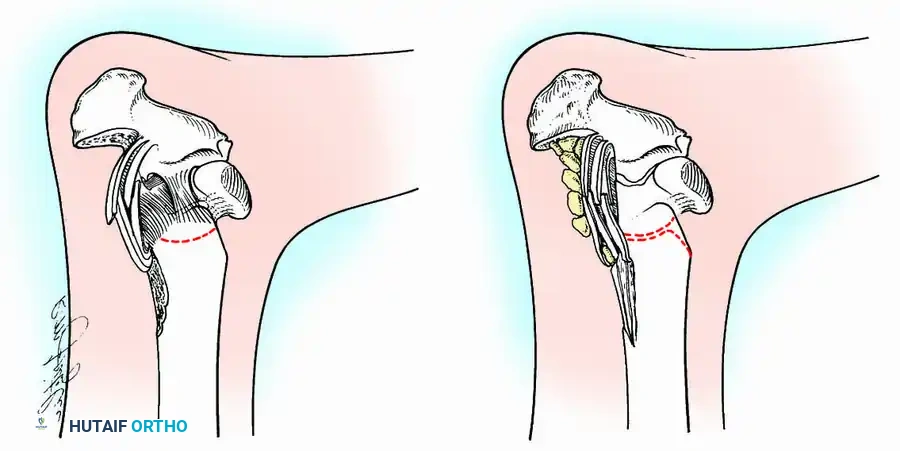

Knee Arthrodesis

While total knee arthroplasty (TKA) is the definitive treatment for knee osteoarthritis, knee arthrodesis remains a critical salvage procedure. The primary indications are a chronically infected TKA that has failed two-stage revision, massive extensor mechanism disruption, severe neuropathic arthropathy, and tumor resection.

Positioning and Technique

The optimal position for knee arthrodesis is 10 to 15 degrees of flexion and 5 to 7 degrees of valgus. This slight flexion assists in foot clearance during the swing phase of gait and makes sitting in confined spaces more manageable. A perfectly straight (0 degrees) knee is cosmetically awkward and functionally detrimental, causing a vaulting gait pattern.